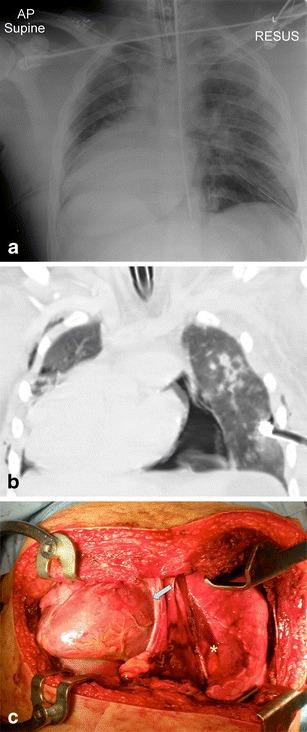

Thoracic injuries are the third most common injuries in trauma patients with cardiac injuries amongst the most lethal. Imaging is essential in diagnosis and triage of patients with pericardial injuries, and this review aims to highlight the spectrum of imaging findings of pericardial trauma. Focussed assessment with sonography for trauma (FAST) is the preferred initial examination, being rapid and accurate. Sensitivity of FAST for pericardial fluid detection is high with reported sensitivities of 97-100%. Plain chest radiography has low sensitivity for pericardial injuries but is useful in the evaluation of associated injuries. Computed tomography (CT) is the modality of choice for stable patients and can accurately diagnose traumatic pathology of the pericardium being especially useful in identification of cardiac herniation. The spectrum of CT findings includes pericardial fluid collections, focal pericardial defects and pneumopericardium.

A selection of cases of pericardial trauma encountered at a level one trauma centre is presented. Operative findings were correlated with the FAST scan, plain radiography and computed tomography imaging.

The imaging findings of pericardial trauma with various imaging modalities (ultrasound, plain radiography and computed tomography) are presented in order to aid interpretation during the acute trauma setting.